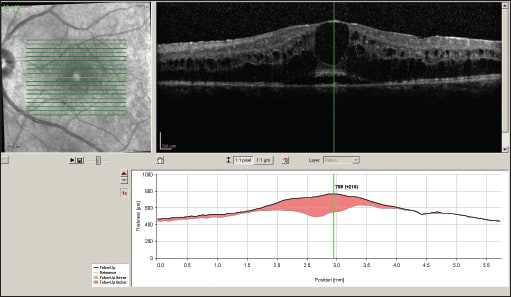

On examination, best-corrected visual acuity was 20/200 OU. Dilated fundus exam revealed 1+ cells in the anterior vitreous of both eyes, early PSC cataract and florid CME in both eyes. In addition, both eyes showed arteriolar attenuation and subtle non-pigmented chorioretinal lesions. Her work up was significant for a positive HLA-A29 haplotype, and OCT confirmed CME in both eyes (Figure 1).

Figure 1. OCT scans of the left eye (top image) and the right eye (bottom image) at time of presentation.